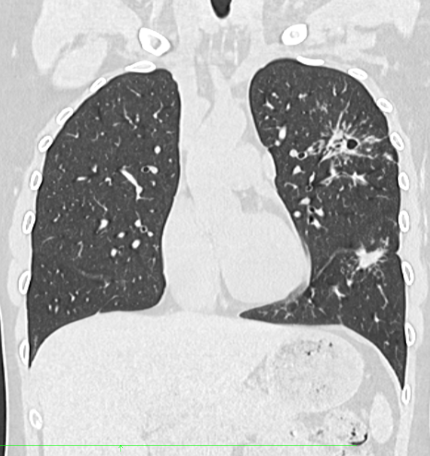

轴位HRCT示左肺上叶可见星系征,中央可见空洞。

冠状位重建HRCT示多个结节影被多个淋巴分布的微小结节包围,呈现“星系征”外观。

冠状面 MIP 重建示“星系征”。

本例患者表现为急性多系统结节病,肺部受累伴典型异常,以及左上叶空洞性结节伴“星系征”。

这种类型的结节由众多小尺寸结节汇聚而成,周围环绕着微小的卫星结节,形成独特的“星系征”。